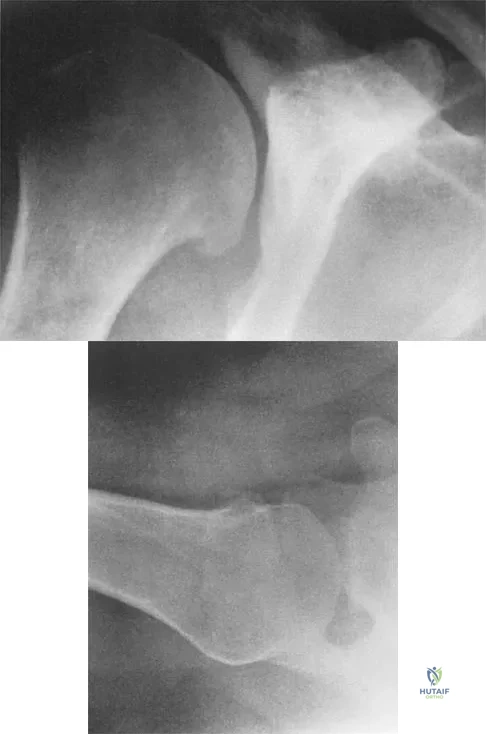

Question 32

Figures 4a and 4b show the radiographs of a 32-year-old man who has right groin pain with activity or prolonged standing. Which of the following factors would not prohibit consideration of acetabular liner exchange and grafting of the defects?